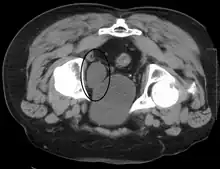

Investigations performed usually include collecting a sample of urine for an inspection for malignant cells under a microscope, called cytology, as well as medical imaging by a CT urogram or ultrasound.[29] If a concerning lesion is seen, a flexible camera may be inserted into the bladder, called cystoscopy, in order to view the lesion and take a biopsy, and a CT scan will be performed of other body parts (a CT scan of the chest, abdomen and pelvis) to look for additional metastatic lesions.[29]

Some forms of medical imaging exist to visualise the bladder. A bladder ultrasound may be conducted to view how much urine is within the bladder, indicating urinary retention. A urinary tract ultrasound, conducted by a more trained operator, may be conducted to view whether there are stones, tumours or sites of obstruction within the bladder and urinary tract. A CT scan may also be ordered.